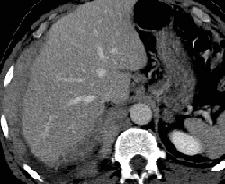

RADIOLOGY: CHEST: Case# 2: MALIGNANT MESOTHELIOMA. 49 year old male with a history of mass in the right hemithorax. A large pleural-based soft tissue mass is seen in the right hemithorax. There is no evidence of liver invasion. Several enlarged right retrocrural lymph nodes are present. While they seem relatively discrete, the vertebral body adjacent to one appears to be eroded or invaded. Mesothelioma is the most common primary tumor of the pleural space. This tumor may be benign or malignant. Malignant mesotheliomas are almost always associated with asbestos exposure. The benign form may be cured by surgical resection, whereas the malignant tumor is aggressive, spreading by local extension, and usually encasing the lung and mediastinum. Prognosis is very poor with a median survival of one year. CT is helpful in establishing the extent of the tumor. Malignant mesothelioma appears as an irregular or nodular pleural thickening surrounding the lung. The tumor is usually visible along the lateral chest wall, however, mediastinal or concentric pleural thickening may be seen in extensive disease. Associated fluid collections, which may be difficult to distinguish from mesothelioma, may be visualized by using contrast and by performing the CT scan with the patient in the prone or decubitus position. Benign mesothelioma is distinct in that it usually appears as localized, solitary lesions arising from the visceral pleural. It more commonly involves the costal pleural surface but may occur within a fissure. On the other hand, pleural thickening associated with asbestos-related pleural disease usually involves the parietal pleura and appears on the inner costal and vertebral surfaces. This disease is usually bilateral.